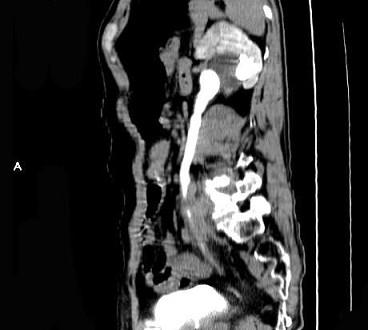

问题 男,59岁,反复尿频尿急尿痛4年余,尿常规检查:红细胞(+),白细胞(++),CT扫描如图示,下列说法正确的是 ( )

选项 A、考虑为慢性输尿管炎 B、考虑为输尿管移行细胞癌 C、左侧侧输尿管上段扩张 D、考虑为输尿管结核 E、左侧输尿管中下段输尿管管壁增厚,管腔狭窄

答案 ACE